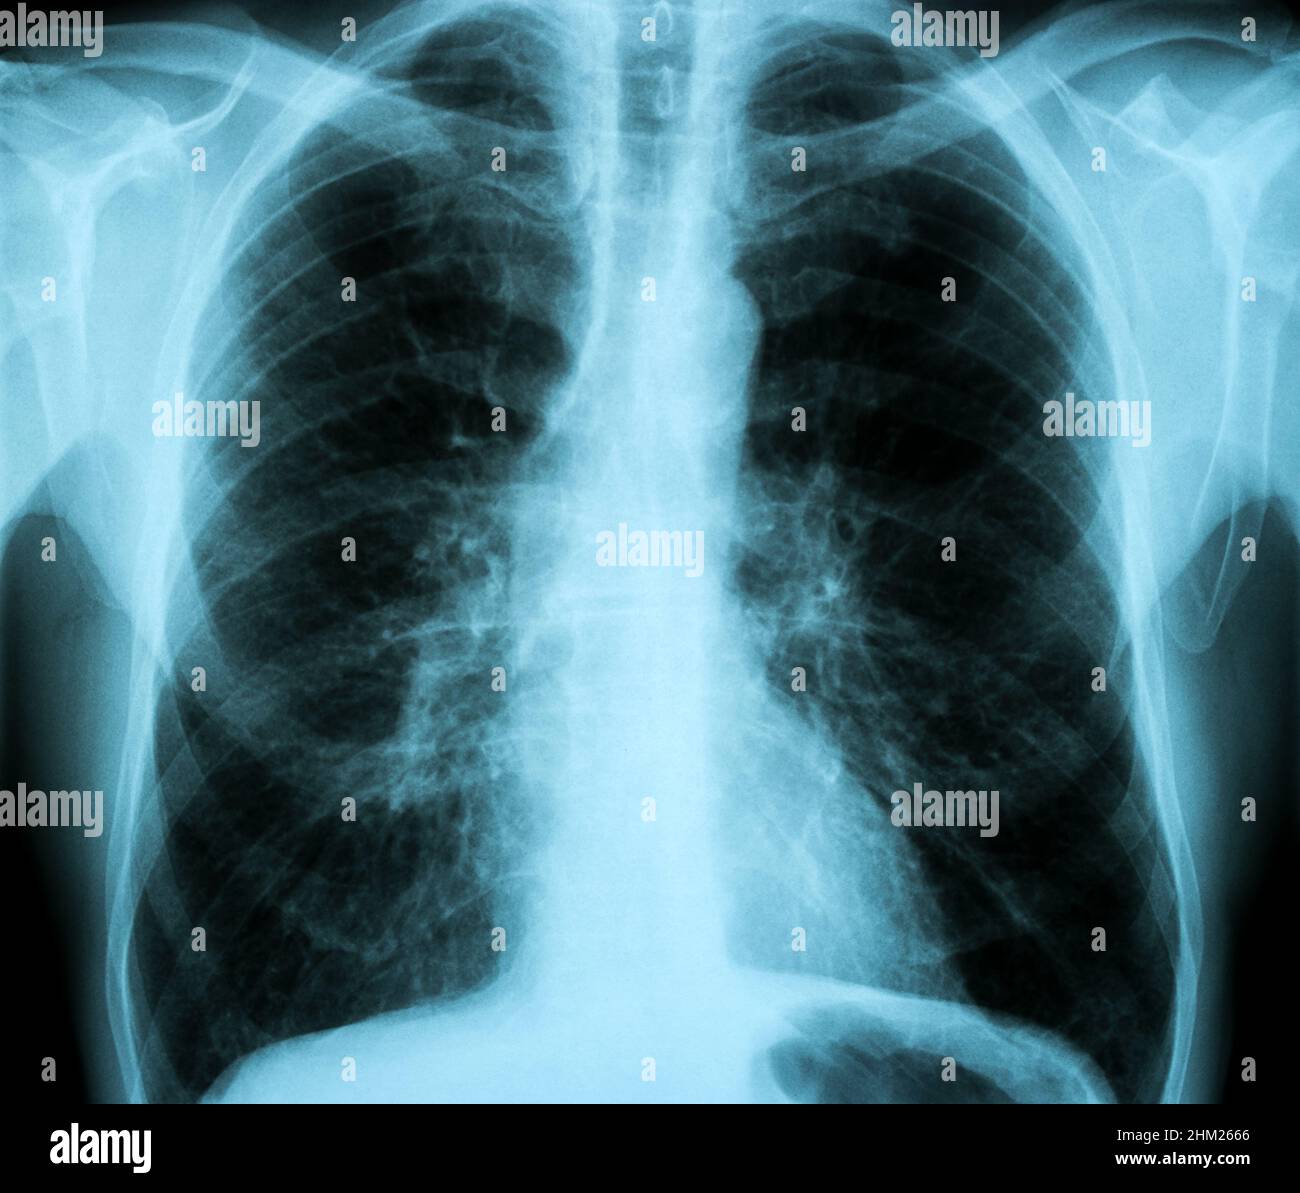

XRay Image of Human Healthy Chest MRI Stock Photo Alamy Why Do I Need A Chest Mri   a special form of mri called magnetic resonance angiography (mra) is helpful to assess the vessels of the chest cavity (arteries and veins).   a heart mri scan can show several aspects related to the heart’s overall health, including how blood flows through the arteries and veins.   discover the importance of mri in detecting lung diseases, heart conditions,. Why Do I Need A Chest Mri.